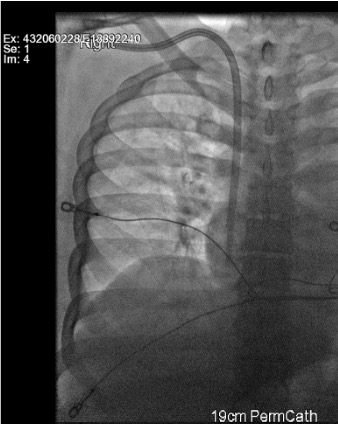

View wire in IVC

Fluoroscopy showing 0.018 wire looping in IVC confirming venous access